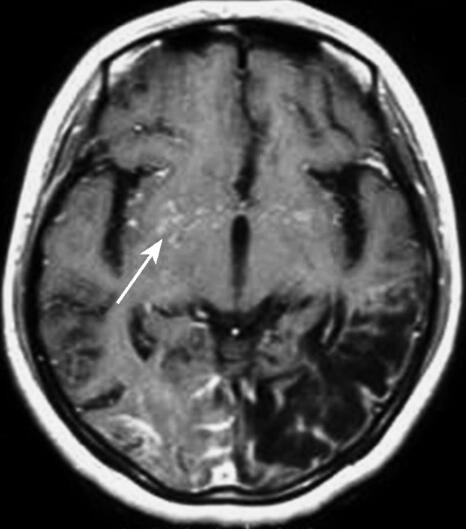

颅脑MRI:左侧颞顶枕叶长T1、长T2信号(2006年1月3日);颅脑MRI,右枕叶长T1、长T2信号,DWI可见高密度影,左侧颞顶枕叶长T1、长T2信号(2006年10月25日)(图1)。MRA示双侧颈内动脉起始段狭窄、大脑前中后动脉显影不良。

图1 颅脑MRI强化检查轴位像示双侧鞍上池周围、外侧裂、基底节区多发细小血管见强化(箭头)

本例患者以上呼吸道感染和发热为首发症状,体温升高持续2周后缓解,随后患者出现口周疱疹,伴有言语障碍、右侧肢体偏瘫。当地医院诊断为病毒性脑炎,虽然1周后患者右侧肢体无力症状明显恢复,但总体治疗效果不明显。2个月后患者逐渐出现智能减退,生活不能自理。9个月后智能严重受损,表现为反应迟钝、自笑、不认识家人。回顾患者发病全过程,我们发现患者的临床表现为急性起病,分别以偏瘫、言语障碍、视力减退为表现形式,经一段时间临床症状可以部分缓解,但总体表现为进行性加重的过程,伴有智能减退,同时抗病毒治疗无效,这些临床表现均不能用病毒性脑炎解释。发病10个月后患者再次出现双眼视物不清,呈发作性,逐渐加重出现双眼完全看不见东西,同时出现反应迟钝、自笑,不认识家人。复查颅脑MRI示右枕叶长T1、长T2信号,DWI可见高密度影,左侧颞顶枕叶长T1、长T2信号。立即行全脑血管造影检查见双侧颈内动脉C2段高度狭窄远段闭塞,大量新生血管呈烟雾状增生。双侧颈外动脉代偿向大脑前动脉供血,基底动脉系统通过皮层支及后胼周动脉向大脑前动脉及大脑中动脉区供血。基底动脉尖和大脑后动脉近段狭窄,大脑后动脉为了代偿性地参与相应缺血区的供血,其远端不断地增生、扩张,遂形成DSA所见的异常烟雾状血管增生。此例患者告诉我们病史和临床体征是神经系统疾病诊断治疗的基础,患者虽然是以上呼吸道感染和发热为首发症状,但几次发作均有血管机制的参与,每次发作后均遗留一定程度的神经系统体征,最后患者出现精神智能障碍。调整诊断思路后发现患者外侧裂、基底节区有多发细小异常血管影像,全脑血管造影检查发现颈内动脉和椎动脉系统均有异常烟雾状血管增生,符合烟雾病的诊断。